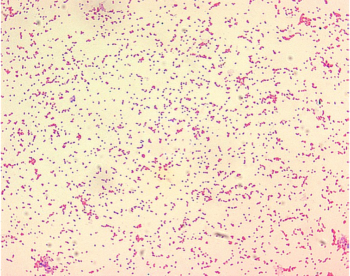

Tra gli agenti di malattia si trovano: virus dell’influenza aviaria, virus dell’influenza delle foche, lagovirus, virus della rabbia, lissavirus dei pipistrelli, filovirus, virus del cimurro canino, morbillivirus dei mammiferi acquatici, virus della febbre catarrale, Virus West Nile hantavirus, virus di Schmallenberg, virus della febbre emorragica Crimea-Congo, virus della peste suina africana, ranavirus degli anfibi, virus dell’epatite E, tubercolosi bovina (Mycobacterium bovis), tularemia (Francisella tularensis), brucellosi (Brucella spp.) (foto), salmonellosi (Salmonella spp.), Coxiella burnetii, chytridiomycosis, Echinococcus multilocularis, Leishmania infantum, Chronic wasting disease (encefalite spongiforme dei cervidi).